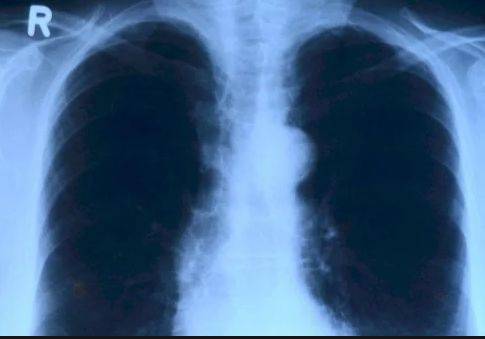

目前,在中国患武汉肺炎死亡人数增至2人,确诊45例。武汉卫生委表示,武汉肺炎的临床表现为发热、乏力等全身症状,伴有干咳,住院患者呼吸困难较为常见,绝大多数患者症状属于轻到中度。